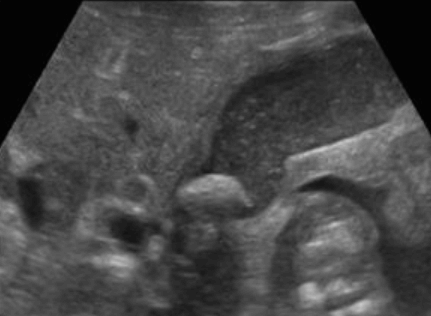

미리찌 증후군 (Mirizzi's syndrom) Mirizzi's syndrom 은 담낭경부, Hartmann's pouch 혹은 담낭관의 결석에 의해 총 간관(CHD)이 폐쇄되는 질환이다. 총 간관(CHD)이 협착되면서 상부담관은 확장되고 하부담관의 직경은 정상으로 나타난다. 증상은 폐쇄성 황달, 복부통증, 발열 등이 나타난다. 급성담낭염이 있으면서 담관폐쇄를 동반할 경우 의심해 볼 수 있다. 담낭절제술 후에 남아있는 담낭관의 결석이 총 간관(CHD)을 직접 누르거나 염증성 협착을 유발하기도 한다.

US finding

- 담낭관 또는 담낭 경부에 결석이 확인된다.

- 총간관(CHD) 또는 담낭관(cystic duct)의 확장소견이 보인다.

- 간내외 담관의 확장이 관찰된다.